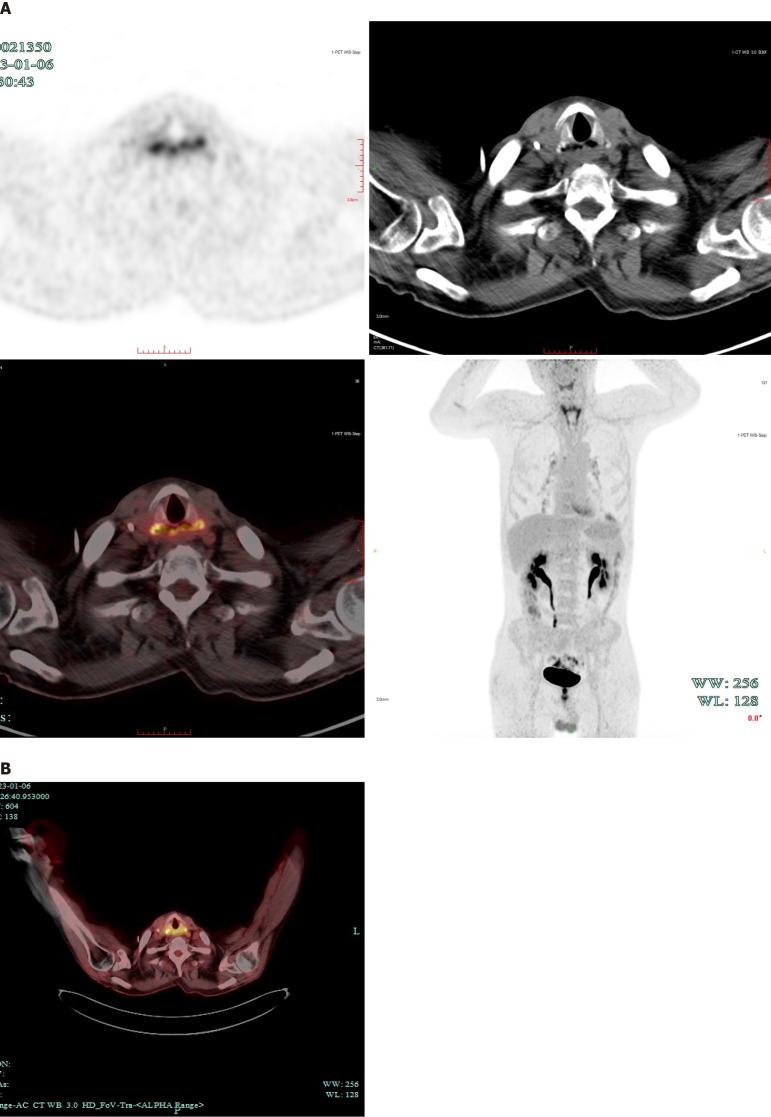

CASE SUMMARY

Here, we present a 59-year-old male patient with a 5-month history of CEC and difficulty eating for over 20 days, who developed TEF secondary to recurrent ESCC after chemoradiotherapy. He underwent total pharyngolaryngoesophagectomy, left thyroidectomy, and lymphadenectomy. Gastric pull-up was performed to restore gastrointestinal continuity, and a 7 cm × 5 cm supraclavicular artery island flap (SCAIF) was used to reconstruct the lower tracheal defect. Despite severe postoperative complications, he recovered by successful management by a MDT. A 7 cm × 6 cm pectoralis major myocutaneous flap was successfully used to repair the necrotic gastric conduit defect. The patient recovered, regaining the ability to eat and breathe effectively. At the 27-month follow-up, he was alive without recurrence or metastasis.

在此,我们报告一名59岁男性患者,有5个月的CEC病史,进食困难超过20天,在放化疗后因复发性ESCC继发TEF。他接受了全喉咽食管切除术、左侧甲状腺切除术和淋巴结清扫术。进行了胃上提术以恢复胃肠道连续性,并使用一块7厘米×5厘米的锁骨下动脉岛状皮瓣(SCAIF)修复气管下段缺损。尽管术后出现严重并发症,但通过MDT的成功管理,他得以康复。一块7厘米×6厘米的胸大肌肌皮瓣成功用于修复坏死的胃管道缺损。患者康复,恢复了有效进食和呼吸的能力。在27个月的随访中,他存活且无复发或转移。